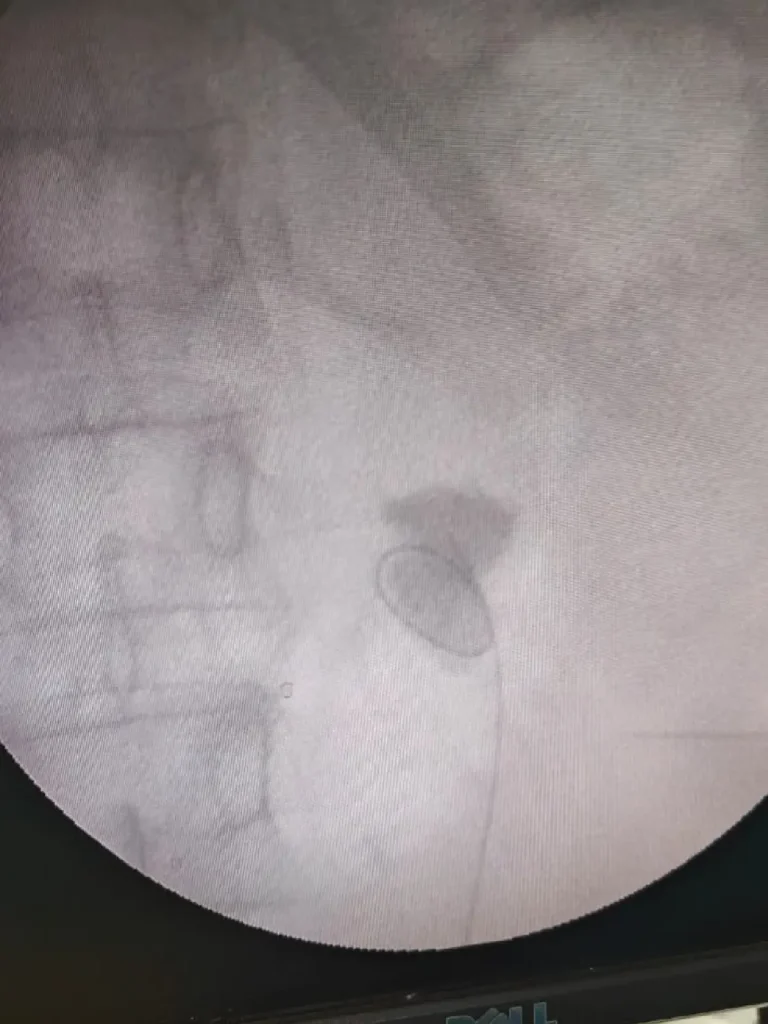

Surgery Photos